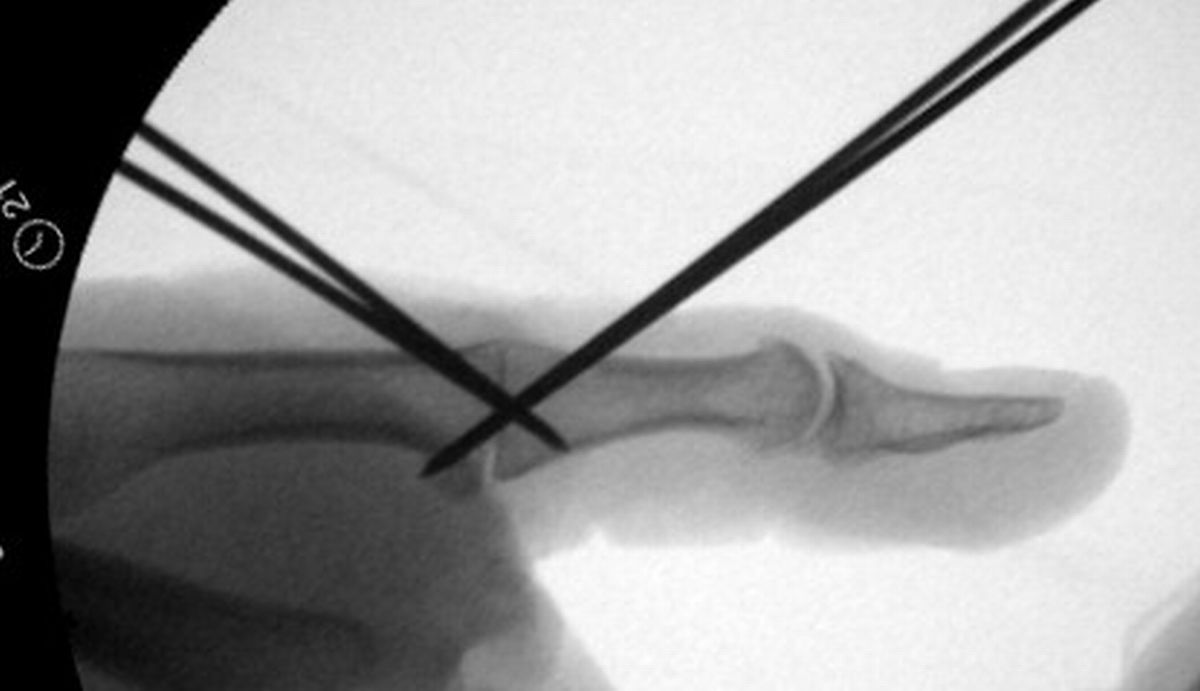

| In this case, 0.045"

K-wires were used for provisional fixation: |

| These were then replaced,

one at a time, with 1.5mm screws. Because of the entry angles, the

countersink bit was used to reduce screw head prominence. |